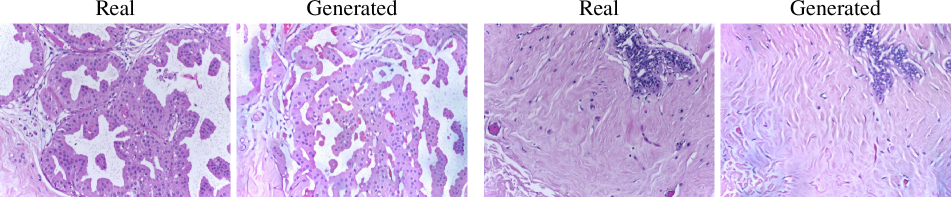

10 Out-of-distribution augmentation examples

In Fig. 7 and Fig. 8 we show out-of-distribution examples of generated images from the NCT-CRC and BACH datasets, along with the reference image from which the SSL embeddings were extracted. For NCT-CRC, it is evident that the synthetic patches follow the semantics and appearance of the real patches used. Regarding BACH, we find the appearance to be slightly different between the real large images and our synthetic large images, but we see that the semantic contents are mostly left unchanged. This is also validated by our augmentation experiments in the main text, where we improve the classification accuracy with synthetic BACH data. In both cases, our SSL-conditioned diffusion models exhibit impressive generalization capabilities by only modifying the conditioning provided to them. Given that generalization is an essential property for building foundation models, we believe that our work is an important step towards this direction for large image domains such as digital histopathology and remote sensing.

Refer to caption

Figure 7: Synthetic images from NCT-CRC. For each generated image we extract the SSL embedding from a real reference image, taken from NCT-CRC-HE-100K, and generate a patch using the TCGA-CRC model. The synthesized patches are similar to the reference in both appearance and semantics. The TCGA-CRC model was never trained on data from the NCT-CRC-HE-100K dataset.

Figure 8: Examples of generated images from BACH. For each generated image we extract the SSL embeddings from a reference image, taken from the BACH dataset. We generate the large image using the TCGA-BRCA model. Although the appearance between the reference and generated images is slightly different, the large images maintain the global semantics. The TCGA-BRCA model was never trained on data from the BACH dataset.